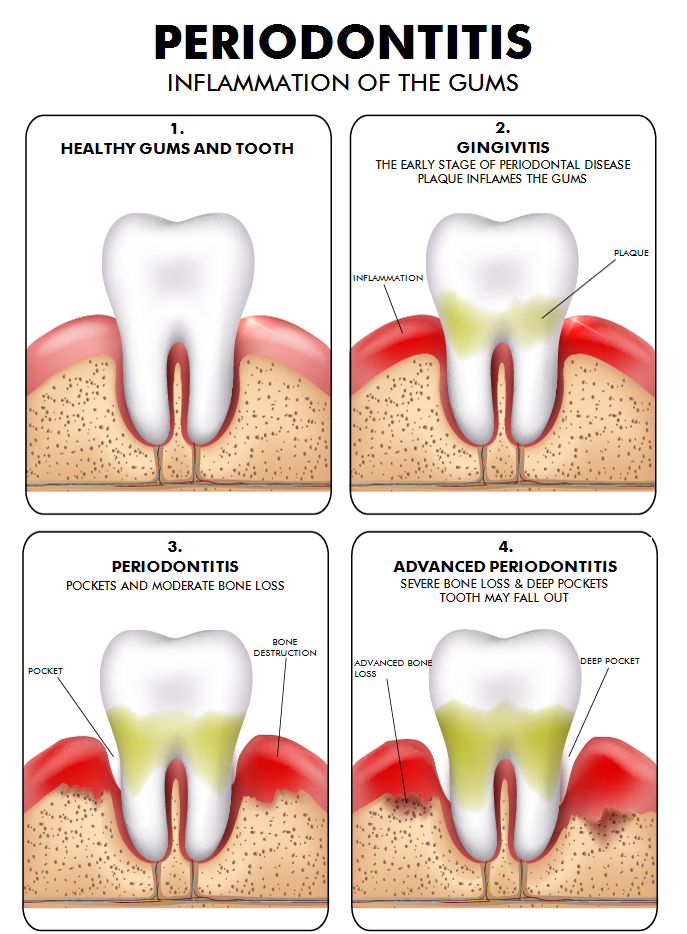

Tooth damage

Of course, there are many ways to damage one's teeth. Two of the most common reasons for tooth damage are periodontitis (inflammation of the gum) and caries (demineralization caused by acids emitted by bacteria). Here are two illustrations to visualize these processes:

The result are partially damaged teeth or loss of teeth.